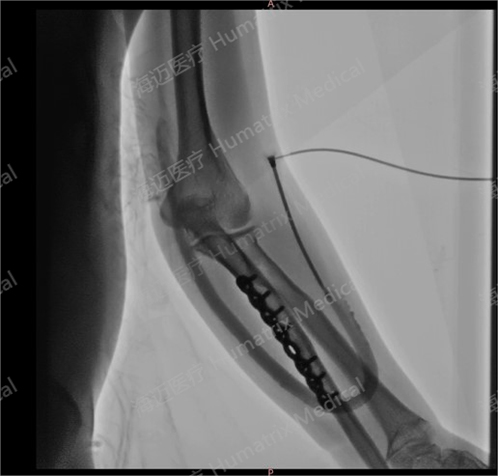

臨床試驗患者使用LineMatrix耐邁通?生物型人工血管長期血液透析,血管造影通暢。

臨床隨訪結果顯示,產品完成植入后,患者術后3月初級通暢率90.9%,累積通暢率100%;術后6月初級通暢率80.8%,累積通暢率100%。人工血管未引發(fā)人體免疫反應,無感染及動脈瘤等并發(fā)癥發(fā)生,產品性能明顯優(yōu)于ePTFE人工血管,臨床效果優(yōu)異。